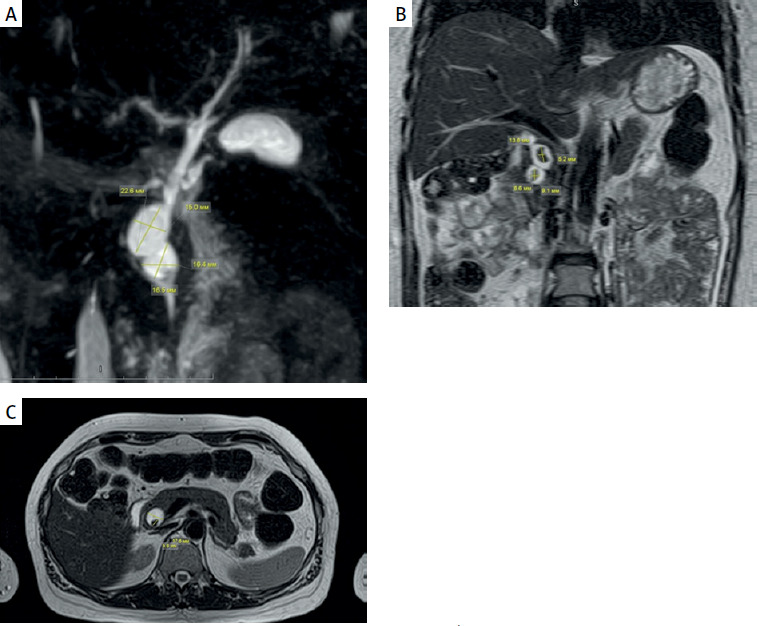

Magnetic resonance cholangiopancreatography (MRCP): Intrahepatic and extrahepatic ducts were dilated; the hepatic duct was 3.5 mm on the right and 3.2 mm on the left. Separate entry points of the segmental ducts S3 and S6 at the confluence. The middle third of the common bile duct was dilated to 6.5 mm, and the lower third was cystically dilated to 22.3 mm. The walls were unevenly thickened, particularly in the lower third, and the lumen was heterogeneous. Type I according to Todani classification. Stones were identified in the lower third of the common bile duct, measuring 12.0 × 10.0 × 5.5 mm and 15.0 × 7.8 × 5.2 mm (Figure 2).

Figure 2

Magnetic resonance imaging (MRI) of the abdominal organs and magnetic resonance cholangiopancreatography (MRCP), showing a choledochal cyst and stones indicated by arrows: A – MRCP: In the distal third of the common bile duct, cystic dilatations are identified (choledochal cyst type I according to Todani) . B – Abdominal MRI (T2-weighted image, coronal slice): In the distal third of the common bile duct, stones are observed within the cystic dilatation. C – Abdominal MRI (T2-weighted image, axial slice): cystic dilatation of the common bile duct (choledochal cyst type I according to Todani) with stones inside